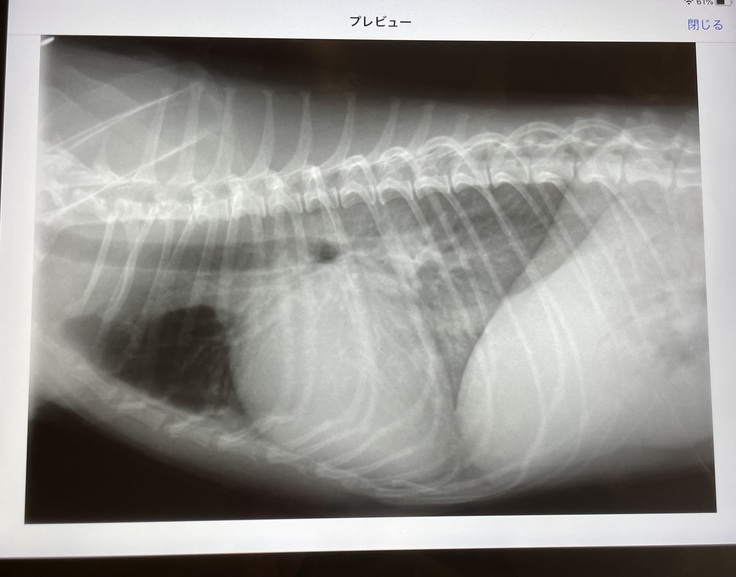

獣医師の説明によれば、姫芽は心不全と肺水腫をおこしており

早急に治療しないと命が危ない状況

肺水腫とは

肺の中に水が溜まってしまい呼吸がしにくくなっている状態。

例えるなら、陸の上で溺れているような苦しさであるということでした。

肺水腫になってしまうと、僧帽弁閉鎖不全症のステージCまで進行してしまい、9ヶ月後の生存率は50%程だそうです。

姫芽は僧帽弁閉鎖不全症と診断されて

3日でステージCまで進行しているということでした。

↑肺に水が溜まっている時のレントゲン